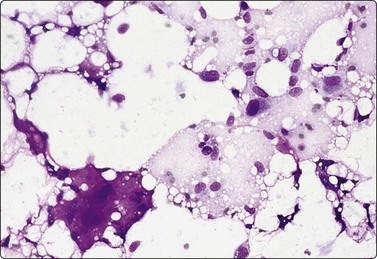

Fat necrosis (Fig. 7.19)

image image image

Fig. 7.19 Fat necrosis

(A) Postoperative fat necrosis. Necrotic tissue, debris and macrophages; fragment of adipose tissue upper right (MGG IP); (B) Fragments consisting of altered adipocytes, macrophages and fat droplets (MGG, IP); (C) Several multinucleated histiocytes with foamy cytoplasm (MGG, HP).

Absence of epithelial cells.

Postoperative changes in response to prior surgical excision or biopsy give similar findings. Fat necrosis is always in the differential diagnosis of nodules in scars or chest wall after surgery, particularly mastectomy. Vigorous or repeated palpation of breast tissue or previous aspiration of the site can result in the same changes. The aspirate is usually scanty, sometimes of oily fluid, and consists mainly of fat with some foamy macrophages or altered, vacuolated adipocytes and multinucleated histiocytic giant cells. The untidy background of granular debris represents the actual necrosis and is the most specific diagnostic feature (Fig. 7.19A,B).

The dispersed presentation of macrophages, particularly if the cytoplasm is dense or nonvacuolated and the nuclei are large with an irregular shape and prominent nucleoli, may mimic a malignant cell pattern, particularly in air-dried MGG smears. Multinucleate forms and foamy cells with similar morphology are helpful in preventing error (Fig. 7.19C).102 Conversely, some carcinoma cells may resemble macrophages. Immunostaining or excision is sometimes necessary.